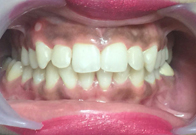

(19)

Before Treatment

After Treatment

Patient reported to us with malalignment of teeth seeking immediate and fast treatment. The case was treated through Inman Aligners taking upto 7 weeks for completion